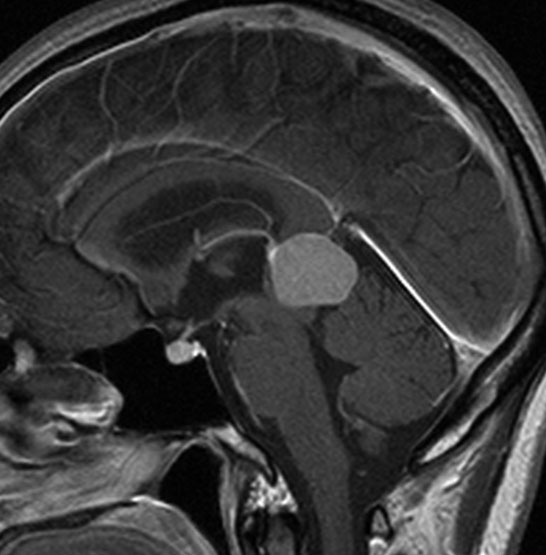

大脳鎌テント接合部髄膜腫 falcotentorial meningioma

30代の女性に発生した髄膜腫です,一見すると松果体細胞腫と見分けはつきません。右の画像に見られるように典型的な中脳水道狭窄を生じていました。

軽度の閉塞性水頭症もありますが,頭痛も無く無症状なので経過を観察しました。髄膜腫だと診断できるのは,右の画像で見られるようにガレン大静脈が右側に偏っているからです。松果体細胞腫の場合は,ガレン大静脈は上方に変位します。

1年間経過観察したら水頭症が進行して脳室が拡大,腫瘍のサイズも大きくなりました。右側の画像で見られるようにガレン大静脈の左側のテントの下面から発生した髄膜腫でした。

左は手術直後の画像です,手術は左側のテント下面を見るために,後頭部経テント法 OTA occipital transtentorial approach で,小脳テントの左側を切断して腫瘍を全摘出しました。右側は6年後の画像ですが,腫瘍再発はありません。

「注意」症状のない患者さんには,なかなか勧められないリスクの高い手術です。この患者さんの場合は無症状で水頭症も軽度で経過観察をしたのですが,本当はそうしてはならないものでした。閉塞性水頭症が急激に悪化して,急性水頭症のために意識障害になる可能性があるものです。